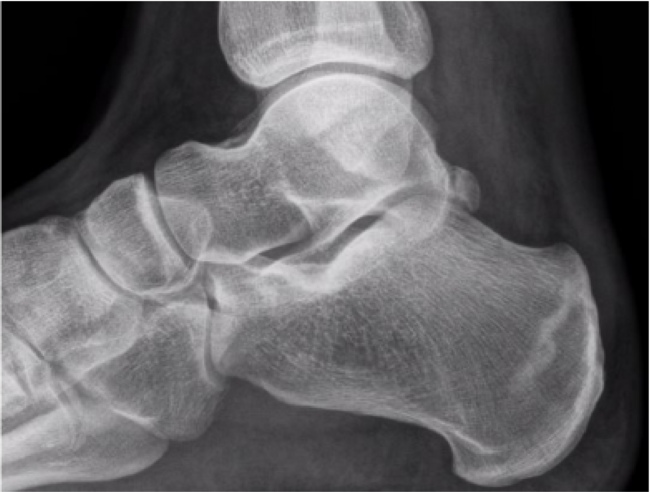

Within this series, 44 were diagnosed solely on X-ray. Those findings are very consistent with sclerosis about the calcaneal body, as shown in Figure 1. More often when you see sclerosis, I find the stress fractures are 3–4 weeks old. Forty-one were diagnosed with MRI after normal X-rays. MRI findings were very consistent, as shown in Figure 2 and Figure 3. Typically, the fracture started along the superior aspect of the calcaneus and propagated plantarly. Only one case started plantarly and propagated dorsally, as shown in Figure 4.